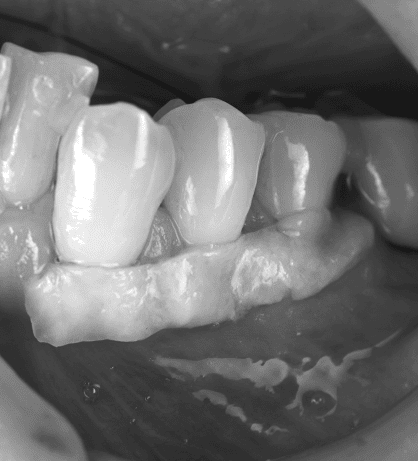

歯肉退縮治療例 治療例1: 40代 女性 ・歯茎が下がってきて、歯が染みてきた 治療前 治療後2年 治療期間 3ヶ月 治療費 5万/1本 (税別) 主な治療内容と概要 根面被覆術(結合組織移植術+歯肉弁歯冠側移動術) 左上の犬歯が伸びてきて染みるということで当院に来院されました。虫歯などはなく、歯茎が下がったことにより根の表面が露出し、知覚過敏の症状がでていました。知覚過敏の改善にはいくつかの方法がありますが、今回は見た目の改善などの患者さんの希望のため、歯肉を移植し、根を覆う処置を行いました。術後から染みの症状はなくなり、歯茎の位置も改善して満足されております。 考えられるリスク・副作用・注意点等 術後の歯肉退縮の再発予防のために決められた指導を守り、継続的なメインテナンスが必要 術後の痛みや腫れなどの症状がでることがあります。(基本的には鎮痛剤の服用などでおさまります) 治療例2: 60代 女性 ・歯ブラシをすると歯茎が痛くて出血する 治療前 犬歯の歯茎だけが大きく下がってしまい、歯の表面が虫歯になりかけている。 治療後1年 歯肉の位置は隣の歯と同様の高さに落ち着き、歯ブラシがしやすい形態に変化した。 治療期間 3ヶ月 治療費 8万/1本 主な治療内容と概要 根面被覆術(歯肉弁側方移動術+結合組織移植術+遊離歯肉移植術) 前歯の一本だけ歯茎が下がってしまい、歯ブラシがしにくい状態になっておりました。そのため、歯茎の炎症と根が一部虫歯に也変えており、今後更に歯茎が下がっていくことが予想されました。組織を移植し、根を覆う処置を行いました。また、硬い歯肉(角化歯肉)が少ないばあい、再発リスクが高くなるため、2回目の手術で硬い歯肉を移植することで、予後が良い状態に改善いたしました。歯肉のラインが横の歯とそろったことで歯ブラシがしやすくなり、現在も良い状態で維持されています。 考えられるリスク・副作用・注意点等 術後の歯肉退縮の再発予防のために決められた指導を守り、継続的なメインテナンスが必要 術後の痛みや腫れなどの症状がでることがあります。(基本的には鎮痛剤の服用などでおさまります) 治療例3: 30代 女性 ・これ以上歯茎が下がるのが不安 治療前 複数の歯の歯茎が下がってしまい、見た目や歯ブラシに影響がでている 治療後5年 歯茎の下がりが改善し、長期的に安定している。 治療期間 3ヶ月 治療費 13万/3本 (止血材込み) 主な治療内容と概要 根面被覆術(トンネリング法+結合組織移植術) 全体的に歯ブラシがお上手でしたが、年齢にしては歯茎が下がってしまい、見た目やブラシング時に不安を感じて来院されました。患者様は今後さらに下がることを恐れており、今回の手術を希望されました。複数歯の歯肉退縮のため、トンネリング法という方法で歯肉の下がりを改善しました。治療後5年たった現在も問題なく不安が解消されたと喜んでおられます。 考えられるリスク・副作用・注意点等 術後の歯肉退縮の再発予防のために決められた指導を守り、継続的なメインテナンスが必要 術後の痛みや腫れなどの症状がでることがあります。(基本的には鎮痛剤の服用などでおさまります) 当院では、歯周病専門医による歯肉退縮(歯茎の下がり)を回復する治療を行っております。 歯茎の位置を元に戻すことで、様々な不具合を改善することができます。また、歯肉を移植する方法を多くとりますが、歯肉を移植することで歯肉の厚みが保たれ、将来的に歯茎が下がることを予防することができます。 矯正治療などにより歯茎が下がった、また歯茎がすでに下がっており、矯正治療できないと言われたなど矯正治療に伴う歯肉退縮改善治療も多く行っています。ご紹介していただく場合は、担当の先生と矯正の開始時期等についてもご相談し、最適な時期に行うことができます。 もしご質問や治療ご希望の患者様はご予約の際に受付にお申し付けください。 歯科鈴木医院 (板橋区桜川 東武鉄道東上本線上板橋から徒歩7分) 2020.12.18 実際の治療例 治療例 本ページでは、当院での実際の治療例を示しております。 各治療例で紹介している治療による結果は個人差があり、治療効果を保証するものではありません。また、起こりうるリスクや副作用等を十分に理解し、担当医と相談して選択し… 2023.05.11 歯周病治療 治療例 歯周病治療例 治療例1: 40代 男性 ・歯医者が怖くてずっと行けていなかった。 ・歯が揺れてきて噛めない ・血が出るので歯ブラシが怖くてできない 治療前 … 2018.06.10 歯周病治療 トップページ 〉診療案内〉歯周病治療 歯周病認定医・専門医とは 歯周組織再生療法 歯周病とは? あなたは以下の項目のどれか当てはまることがありますか? ・朝起きたとき、口の中がネバネバする。 ・ブラッシング時に出…